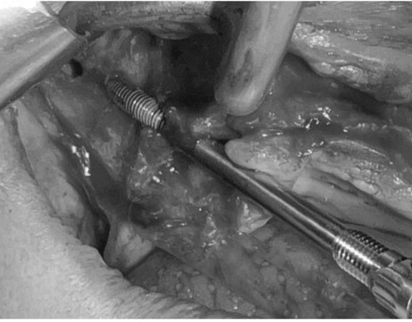

Colocamos los implantes cigomáticos según las guías quirúrgicas que hemos diseñado en planificación 3D.

Podemos hacer carga inmediata. Todo se realiza bajo sedación intravenosa monitorizada